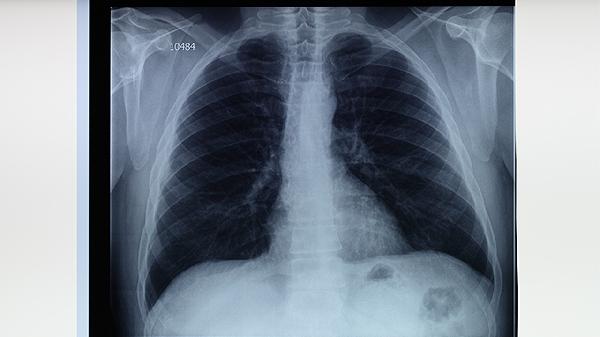

每日体温波动超过1℃,但最低温度仍高于正常值。多提示病灶范围较大或合并其他感染,需通过胸部影像学检查评估病情。治疗需严格遵循抗结核方案,不可自行停药。